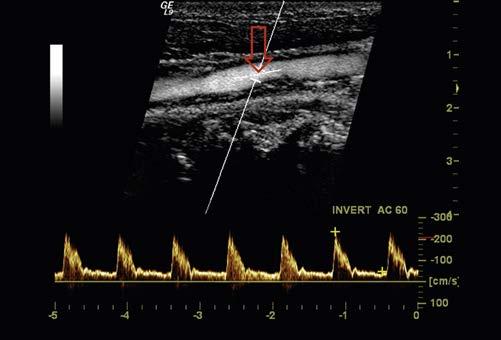

enable color-coded 2D and 3D presentations of Doppler information (color-Doppler displays) to be superimposed on gray-scale anatomic images (Figure 1-13). Doppler information is applied to loudspeakers for audible evaluation and to spectral-Doppler displays for quantitative analysis (Figure 1-14). The spectral-Doppler operation includes

anatomic imaging to determine the location(s) from which the spectral information is acquired (Figure 1-15).

FIGURE 1-14 Spectral-Doppler display of arterial blood flow with presentation of calculated flow velocity data.

FIGURE 1-15 Spectral-Doppler display of blood flow in the carotid artery. The anatomic image shows the location (arrow) from which the spectral-Doppler information was acquired.